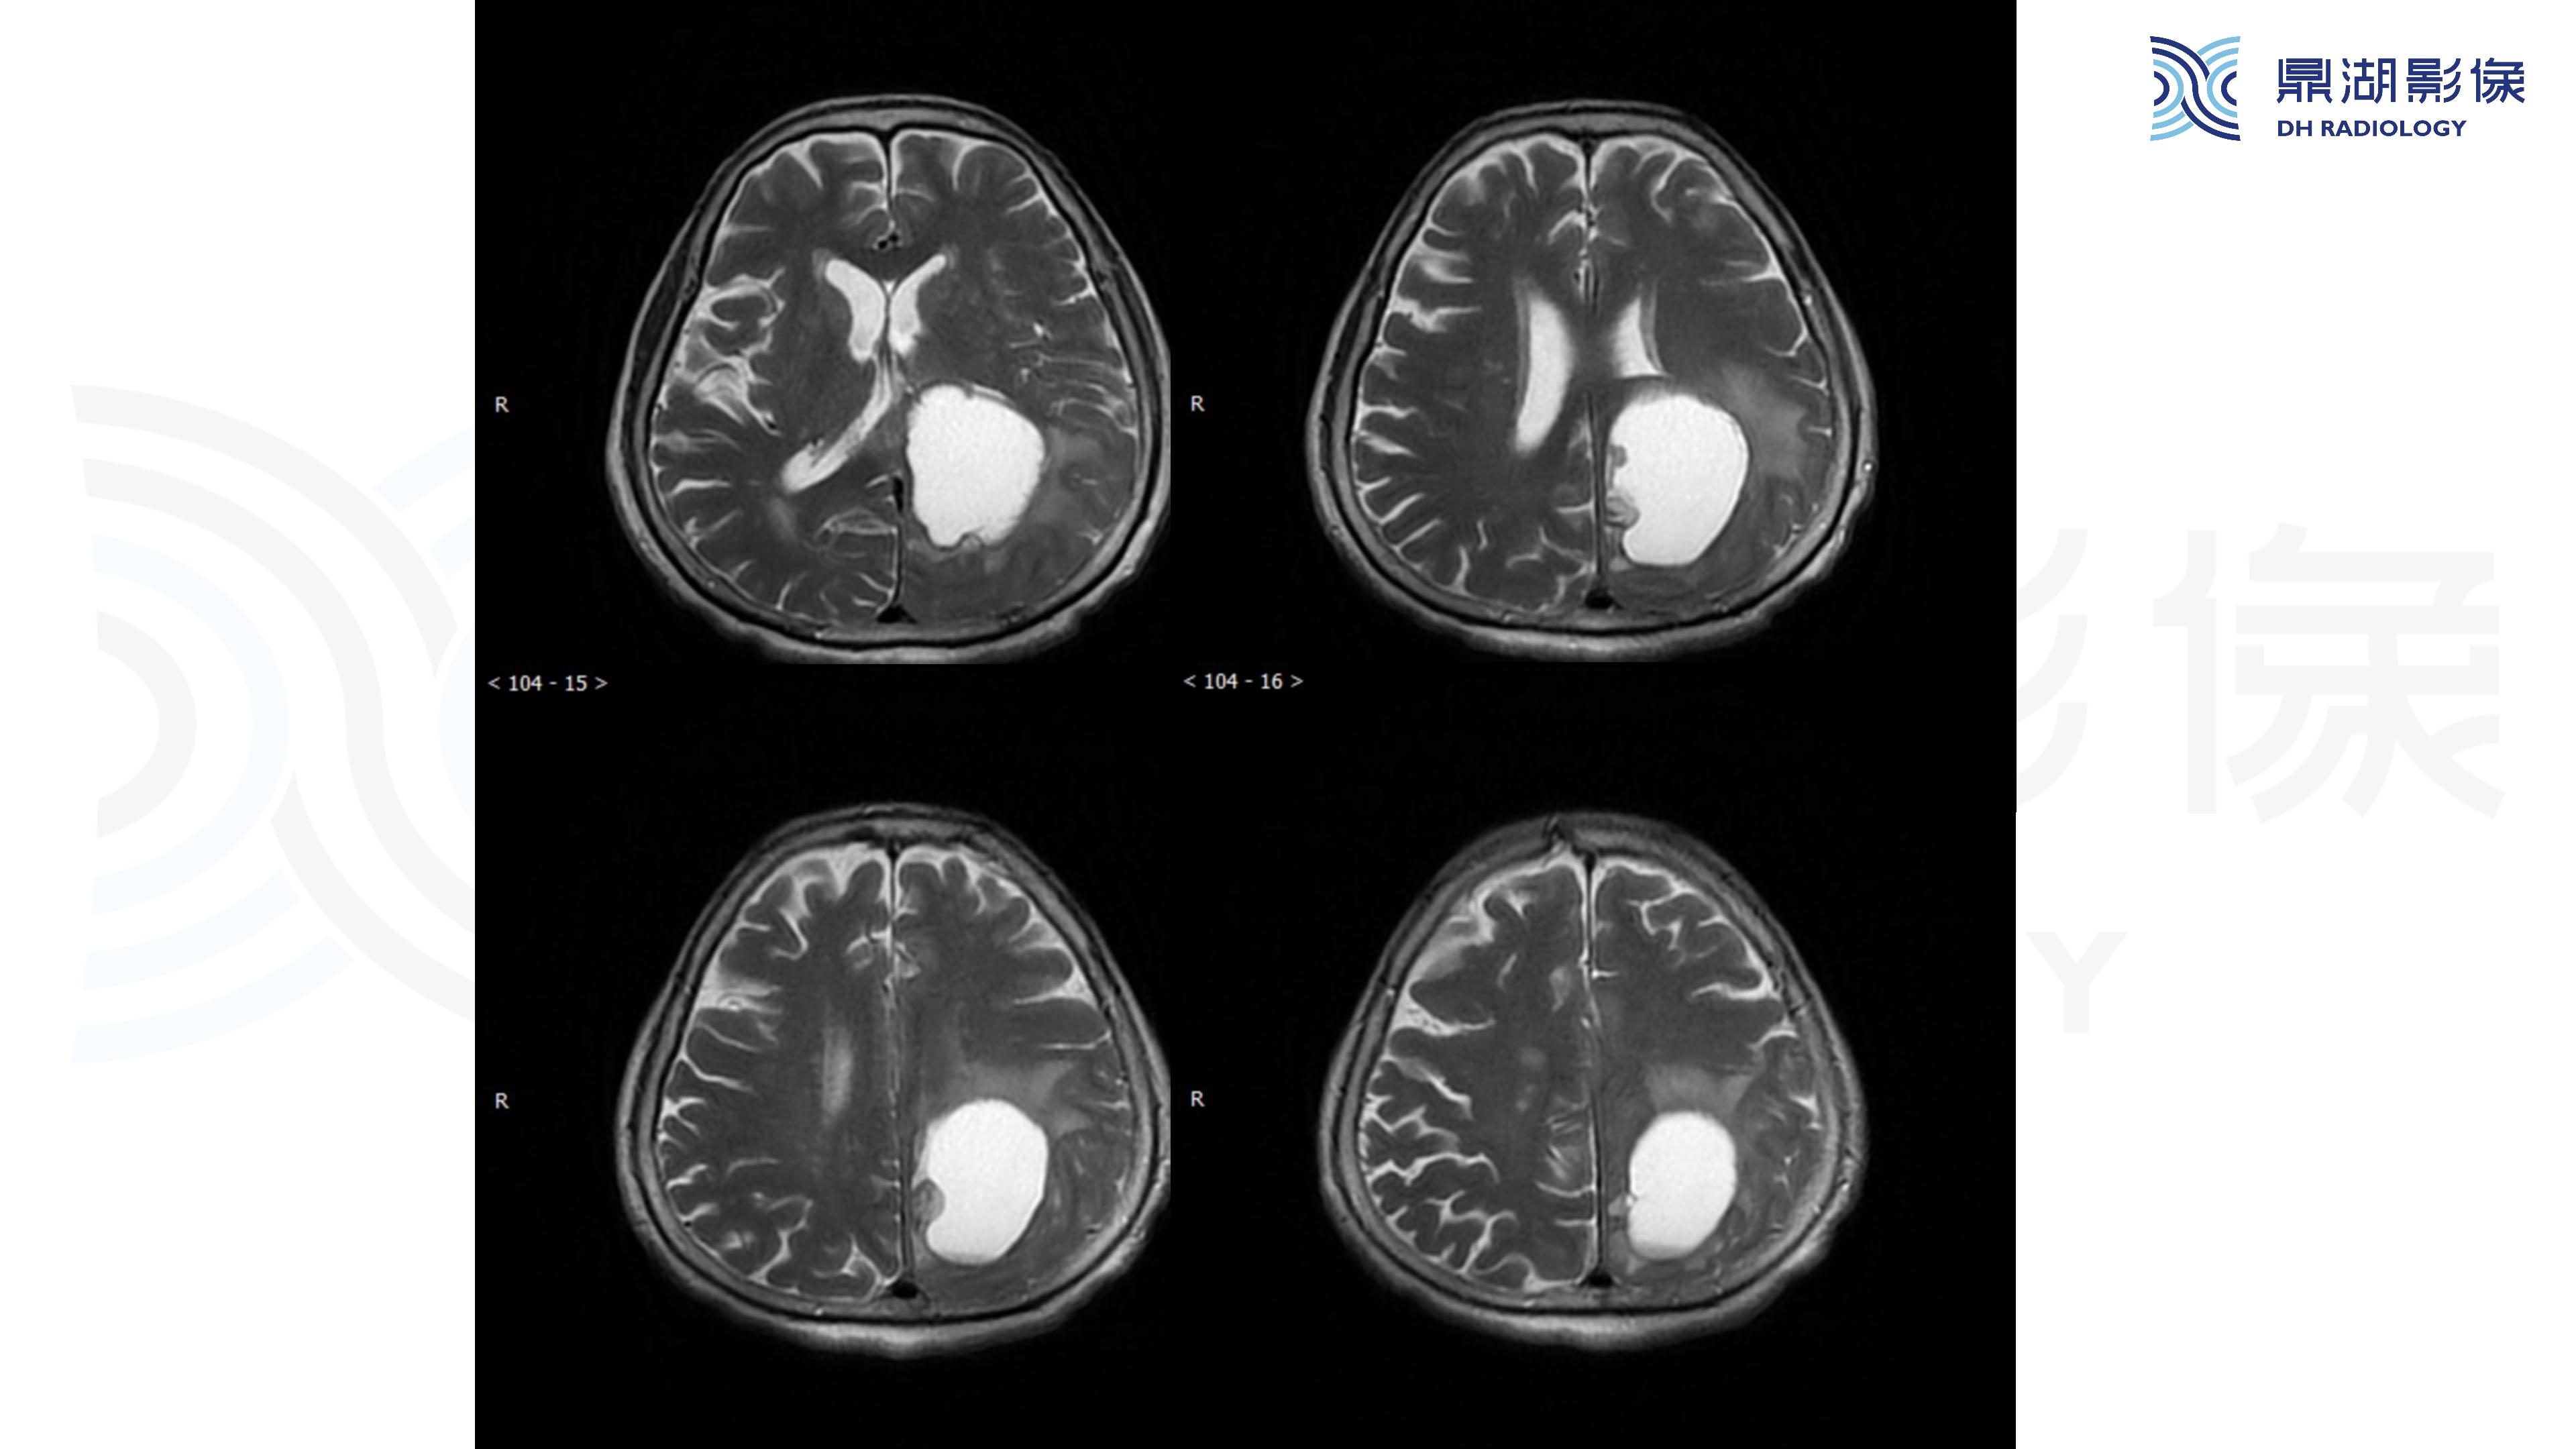

幕上毛细胞型星形细胞瘤(WHO Ⅰ级)